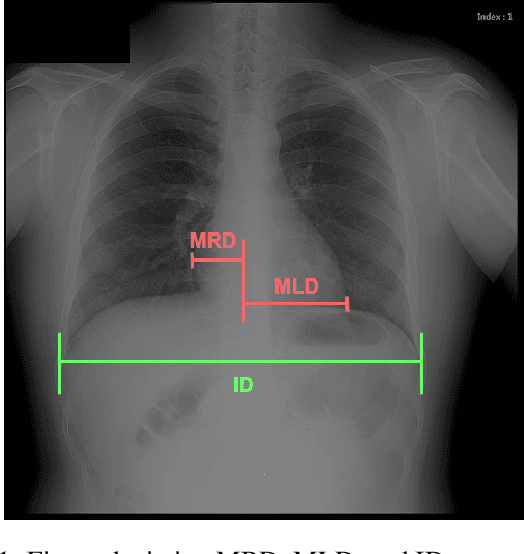

We propose an algorithm for calculating the cardiothoracic ratio (CTR) from chest X-ray films. Our approach applies a deep learning model based on U-Net with VGG16 encoder to extract lung and heart masks from chest X-ray images and calculate CTR from the extents of obtained masks. Human radiologists evaluated our CTR measurements, and $76.5\%$ were accepted to be included in medical reports without any need for adjustment. This result translates to a large amount of time and labor saved for radiologists using our automated tools.